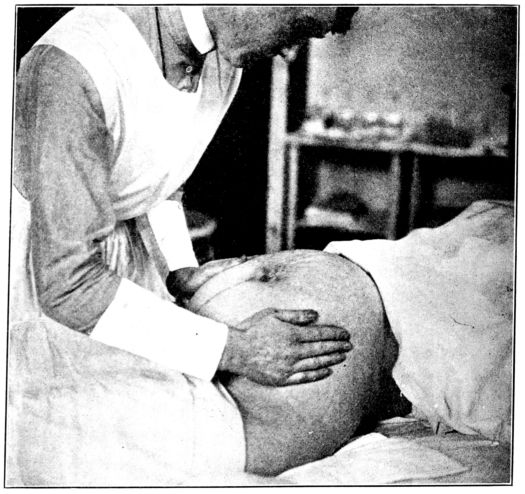

| 57. | First maneuver in abdominal palpation | 225 |

| 58. | Second maneuver in abdominal palpation | 226 |

| 59. | Third maneuver in abdominal palpation | 227 |

| 60. | Fourth maneuver in abdominal palpation | 228 |

| 61. | Diagrams showing positions of nurse’s hands in four maneuvers of abdominal palpation | 229 |